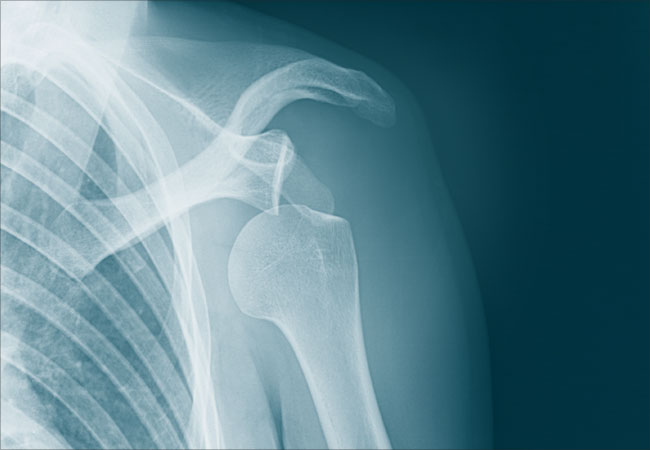

Вывих плеча (на фото можно увидеть, как это выглядит) является серьезной травмой, требующей срочного медицинского вмешательства. Чтобы установить факт вывиха, необходимо обратить внимание на ряд характерных симптомов. Ниже перечислены основные признаки повреждения плечевого сустава:

- Перелом костей. Возникает в тех случаях, когда суставная капсула не просто повреждается, а разрывается. Определить такое повреждение с помощью внешних симптомов будет довольно трудно, поэтому не стоит пренебрегать возможностью сделать рентген. Как правило, перелом сопровождается острой и очень сильной болью, а также отсутствием возможности пошевелить плечом. При пальпации может наблюдаться хруст обломков костей.

- Рентгенография в двух проекциях. Эта процедура позволяет не только оценить степень вывиха и направление кости, но и исключить вероятность внутреннего перелома. Зная точное положение кости у пациента, врач сможет выполнить вправление более эффективно и с минимальной болью. Также рентген может выявить наличие опухолей, возникающих при длительном отсутствии лечения смещенной конечности.